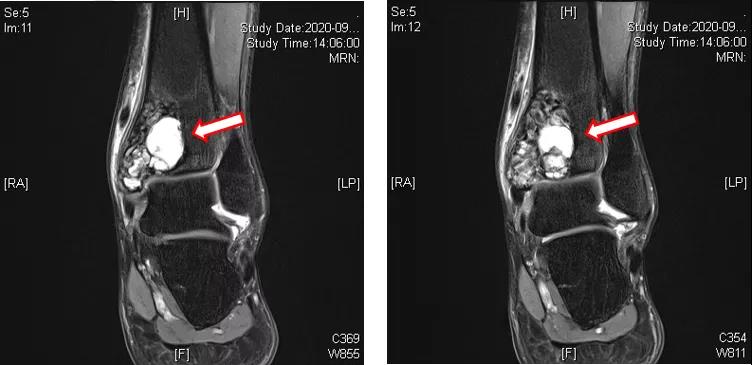

辅助检查:左踝MRI(2020-09-03):左侧胫骨内侧髁关节面下见团块状T1WI等信号、T2压脂不均匀高信号影,内见多发囊腔;病变大小约为27 mm(前后)×39 mm(左右)×45 mm(上下),边界清楚,病变后缘向后膨隆,周围软组织见条片状压脂高信号影(T2WI脂肪抑制序列病变周边高信号),环绕胫骨下端周长2/3。左侧胫骨内侧髁关节面下占位性病变,考虑骨巨细胞瘤可能性大(图1~3)。

图1:左踝MRI(2020-09-03)

图2:左踝MRI(2020-09-03)

图3:左踝MRI(2020-09-03)